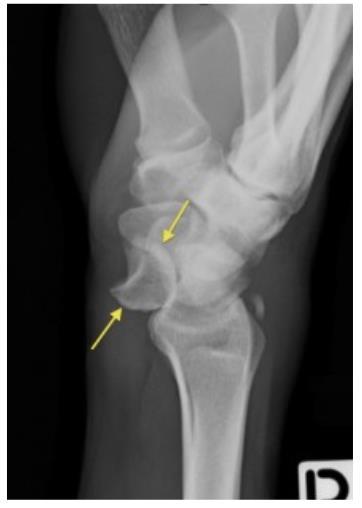

Se ha intentado adaptar la pHmetría como método de estudio para estos síntomas colocando el sensor de pH en la hipofaringe o cerca de ella con condiciones técnicas cuestionables y baja concordancia y se ha intentado medir la pepsina en saliva como indicador indirecto de reflujo con muy baja sensibilidad (38%) y especificidad (60%) para diferentes entre fenotipos, por lo que a pesar de sus limitaciones teóricas, son la pHmetría convencional y la pH/impedanciometría las únicas pruebas validadas para la aplicación clínica10

Un tratamiento eficaz implica un enfoque multidisciplinario destinado a identificar cofactores causales y tratamientos complementarios. Respecto al manejo quirúrgico, no existen datos de alta calidad que respalden su eficacia en estos síndromes10 .

Hay registros anecdóticos de pacientes con reflujo que desarrollan fibrosis pulmonar, bronquiectasias, tos crónica, asma o disfunción laríngea, sin embargo, la ERGE como contribuyente a estos síndromes extraesofágicos no ha demostrado ser un real problema. Una excepción a la regla es la presencia de ERGE en pacientes con trasplante de pulmón, que, a pesar de las dificultades para establecer su causalidad, tiene consideraciones importantes en relación con nueva enfermedad pulmonar primaria y lesión del aloinjerto asociada a la exposición al ácido incluso con tratamiento con IBP, lo que hace que algunos de estos pacientes que van a ser trasplantados de pulmón, sean llevados previamente a funduplicatura de forma preventiva6 .

257